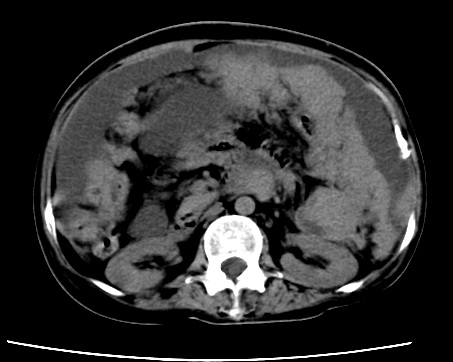

标题: CT23975:女61岁,腹部不适,明显消瘦 [打印本页]

标题: CT23975:女61岁,腹部不适,明显消瘦

既往5年前卵巢癌行子宫及附件切除,右乳癌术后一年,考虑腹膜转移?

大量腹水,考虑腹膜转移。肝脏低密度灶。1囊肿,2转移。

1)结合病史,考虑腹膜及网膜转移瘤。2)肝脏多发性低密度灶,不排除转移瘤。3)大量腹水。

考虑卵巢癌行子宫术后复发,并肝、腹腔 、大网膜转移可能性大。

大量腹水。